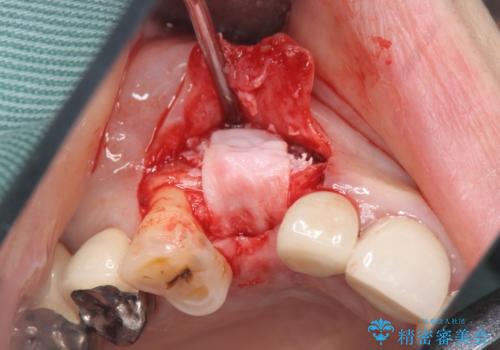

- 45万円(ストローマンインプラント・骨造成・チタンカスタムアバットメント・ジルコニアクラウン)費用は治療当時の料金となります

前歯のインプラントを仕上げるには骨や歯ぐきの条件を整えることが肝要です。